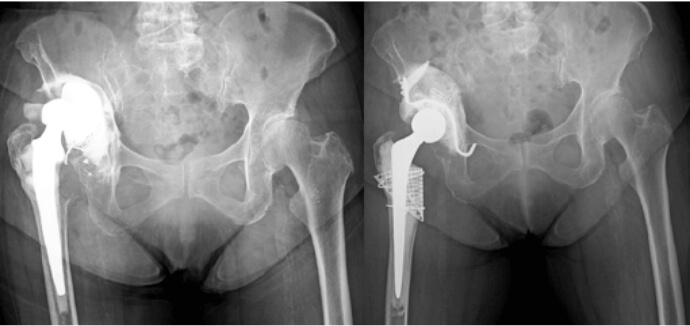

人工股関節全置換術(THA)

3Dテンプレートシミュレーション・Navigation system

THAは股関節疾患の末期像に対して行われる手術法で、関節面の不良な部分を除去し、人工関節に置き換える術式です。寛骨臼側の人工関節はカップまたはソケット、大腿骨の方をステムと呼びます。骨と人工関節の描着には骨セメントを使用する場合としない場合があり、後者をセメントレスと言い、当科の初回THAは大部分を占めます。摺動面における摩耗を減少させるため、ポリエチレン、セラミックや金属などの材料が改良されています。THAにおいては正確なカップやステムの設置が重要ですが、当科では3Dテンプレートによるコンピュータシミュレーションの術前計画と術中にはNavigation systemをすべての手術に使用し、精度を挙げています。

人工股関節再置換術

骨欠損部には同種骨が移植されています。

人工股関節は術後易脱臼性、周囲骨折、骨溶解やゆるみなどの理由から、以前の人工関節を抜去し、新たな人工股関節を設置する再置換術が行われます。初回手術よりも技術的に難しいですが、初回手術と同様、3Dテンプレートによるコンピュータシミュレーションの術前計画と術中にはNavigation systemをすべての手術に使用し、精度を挙げています。骨欠損が生じていることも少なくなく、十分な骨移植を併用しながら、時には補強器具も使用し、股関節を再建しています。